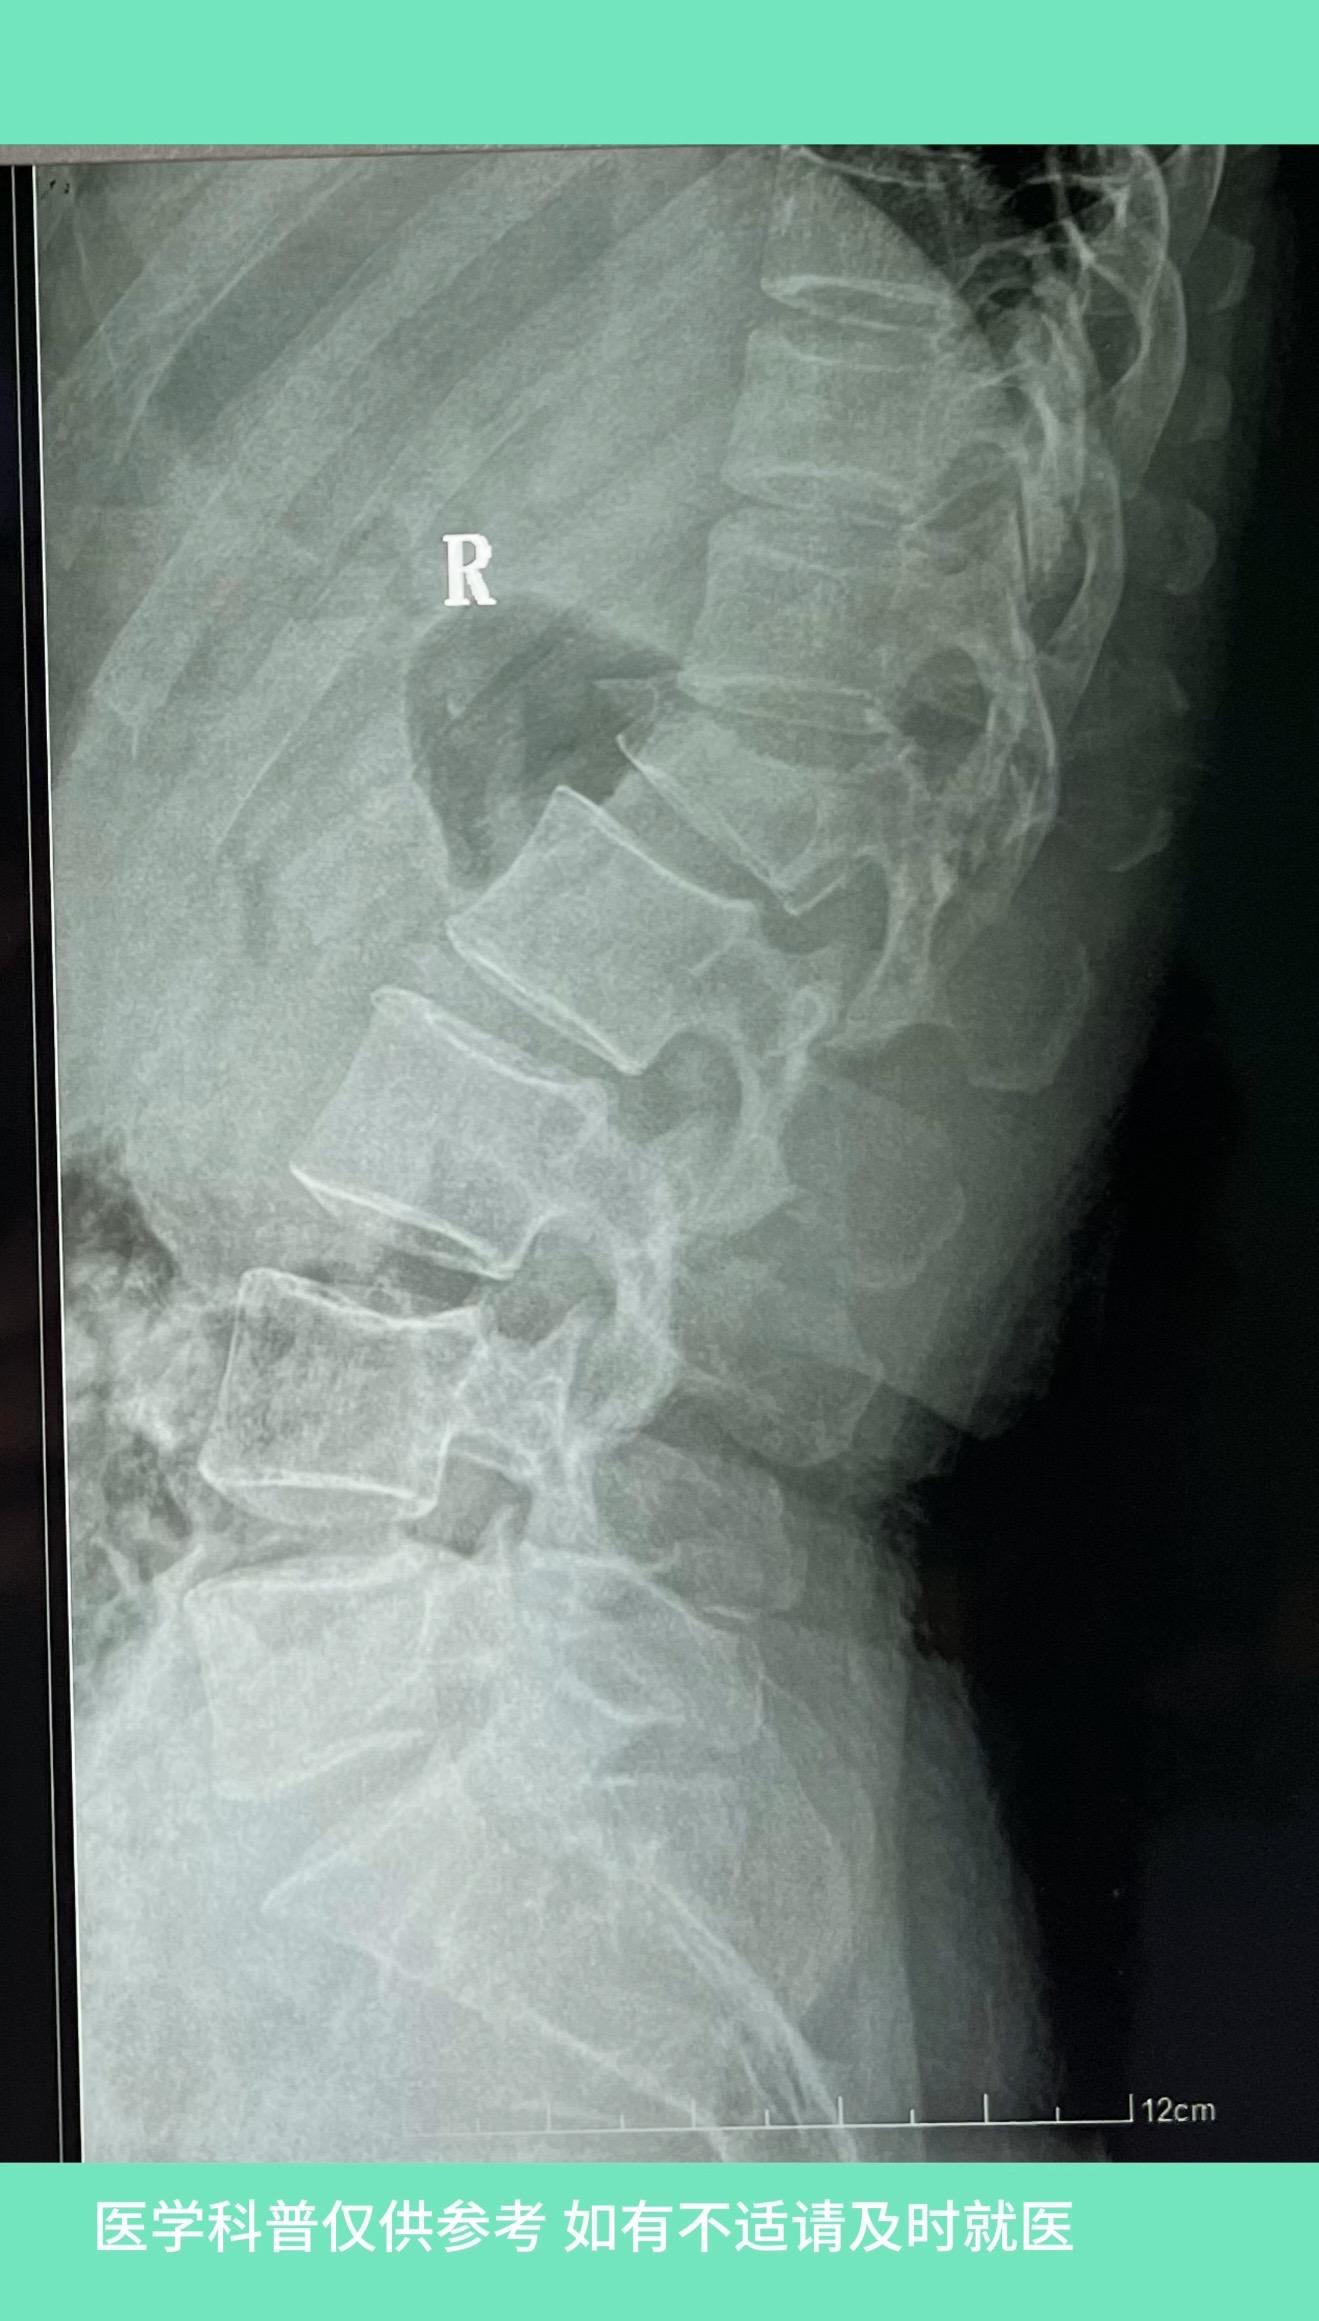

40多岁女性,劳动时从拖拉机上摔下,腰1骨折。磁共振显示脊髓有压迫,但患者无神经症状,就给予单纯固定,未减压,术后恢复好。